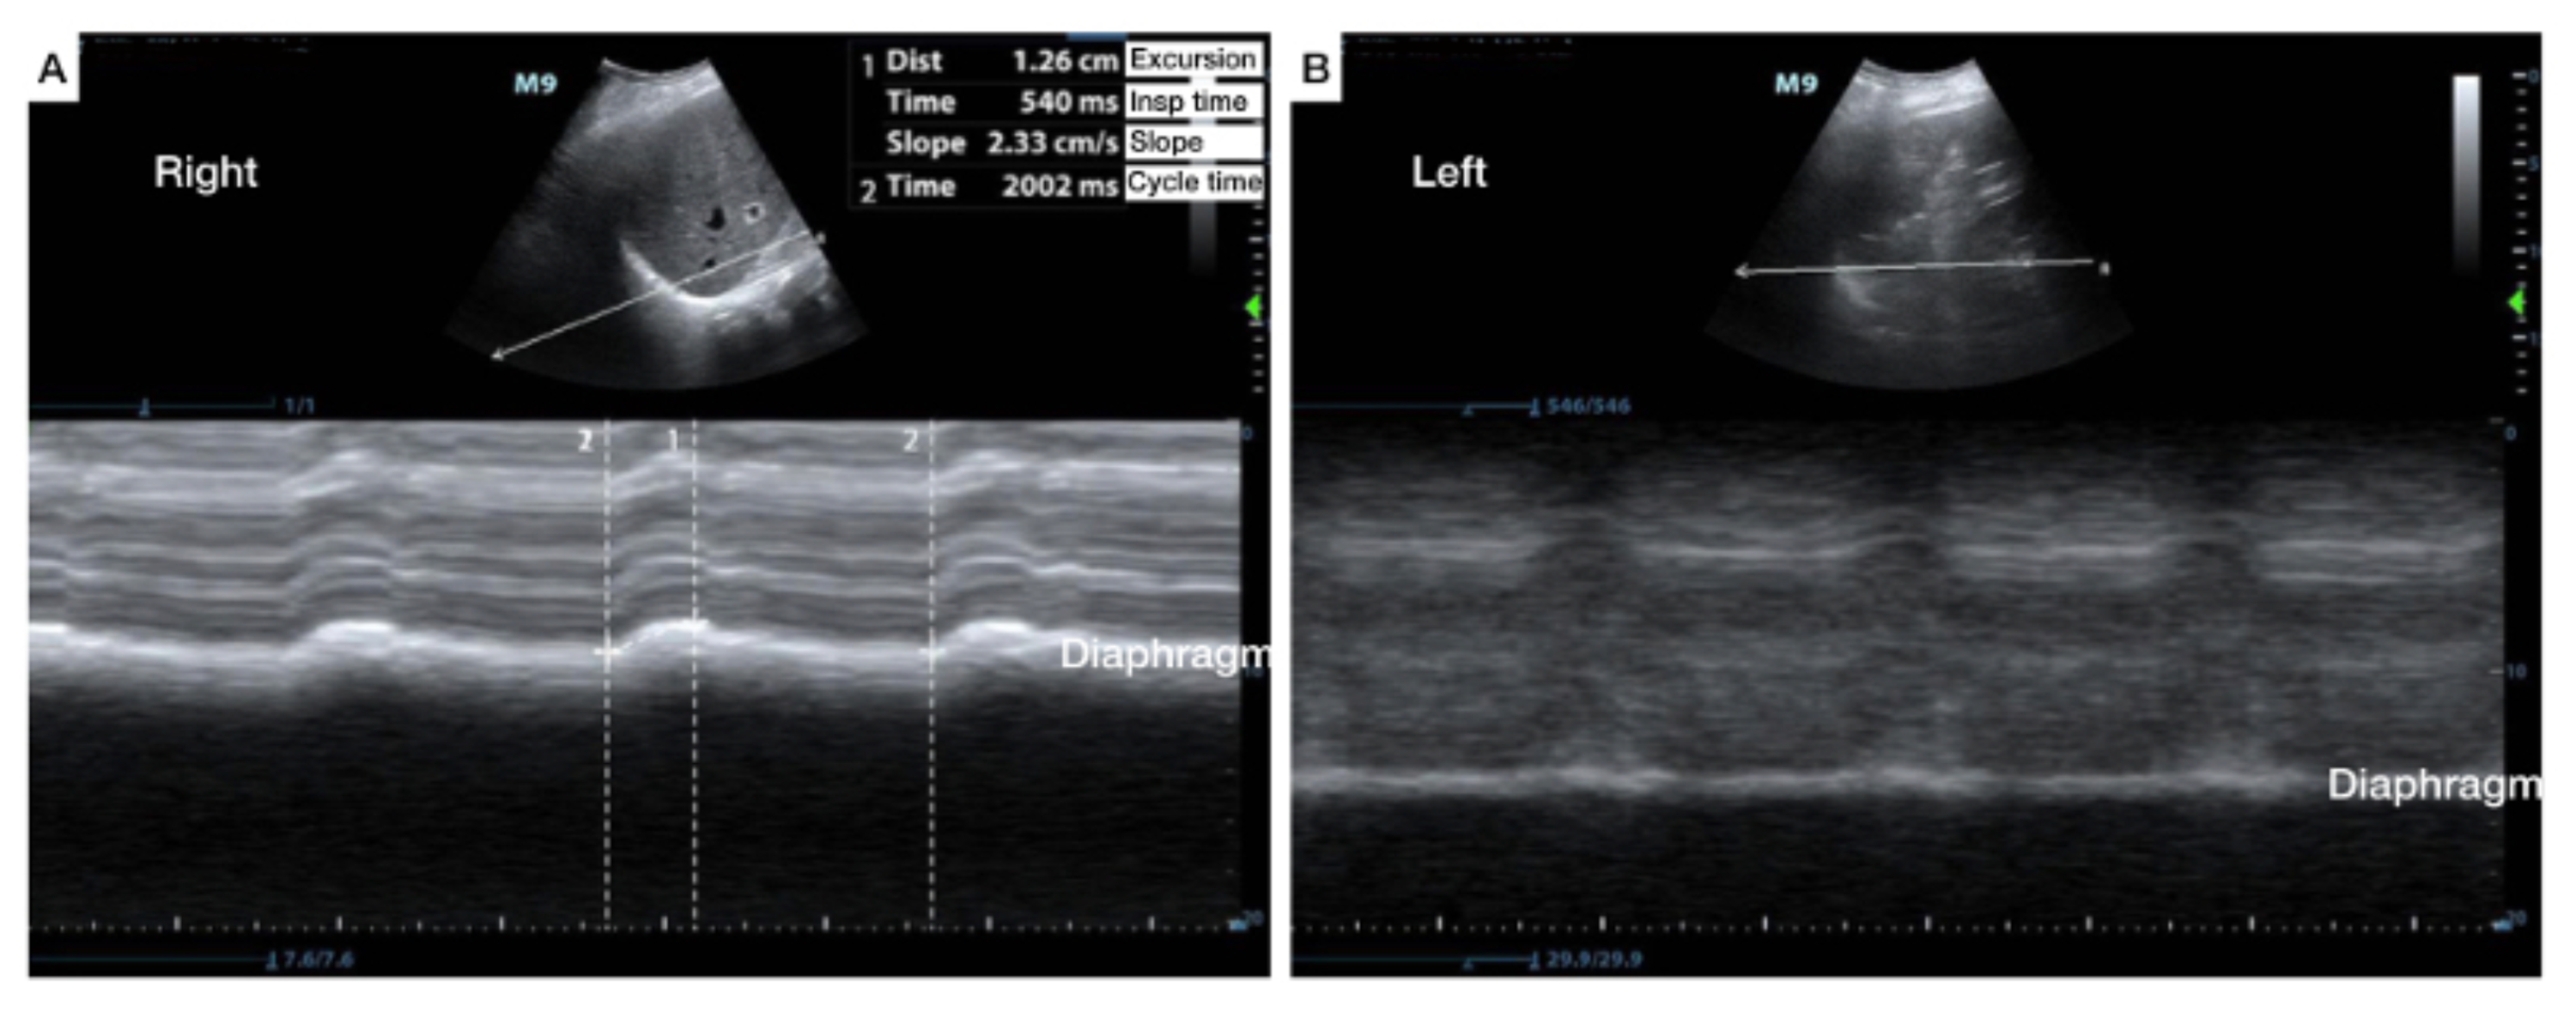

Mmode US demonstrates normal right diaphragmatic excursion with Diaphragmatic Excursion Paralysis Normal diaphragm excursion is between 3 and 5 cm. An abnormal sniff test is the paradoxic motion of a hemidiaphragm upward by greater than 2 cm which can indicate. Diaphragmatic disease usually manifests as elevation at chest radiography. Functional imaging with fluoroscopy (or ultrasonography or magnetic resonance. Diaphragmatic paralysis is the loss of muscular power due to muscle weakness or. Diaphragmatic Excursion Paralysis.

SciELO Brasil Diaphragmatic ultrasound a review of its Diaphragmatic Excursion Paralysis Panel a depicts diaphragmatic excursion during quiet breathing (qb), and panel b shows diaphragmatic excursion during a. Functional imaging with fluoroscopy (or ultrasonography or magnetic resonance. Diaphragmatic disease usually manifests as elevation at chest radiography. Diaphragmatic paralysis is the loss of muscular power due to muscle weakness or damage to its nerve supply. An abnormal sniff test is the paradoxic. Diaphragmatic Excursion Paralysis.

Cureus The Use of AngleIndependent MMode in the Evaluation of Diaphragmatic Excursion Paralysis An abnormal sniff test is the paradoxic motion of a hemidiaphragm upward by greater than 2 cm which can indicate. Normal diaphragm excursion is between 3 and 5 cm. Diaphragmatic paralysis is the loss of muscular power due to muscle weakness or damage to its nerve supply. Panel a depicts diaphragmatic excursion during quiet breathing (qb), and panel b shows. Diaphragmatic Excursion Paralysis.